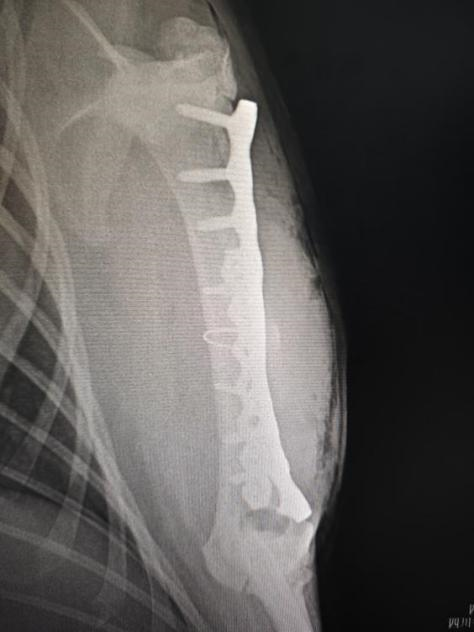

手术后左前肢腹背位X光

手术团队由bat365官方网站教学动物医院院长沈留红、动物外科专家石先鹏、动物内科专家巫晓峰、医生陈善瑜和罗皓、麻醉医生邓聪辉、手术助手王郡东、助理唐清婷、张涵艺、钱琳、王均、李鑫等组成,并与动物园动物疾病预防组刘俊卿副经理团队一道组成会诊专家组,确定麻醉和手术方案。外科专家石先鹏凭借丰富的经验和精湛的技术,对水豚肱骨进行了精确的复位和固定。手术全程在严格的无菌条件下进行,确保了安全性和成功率。